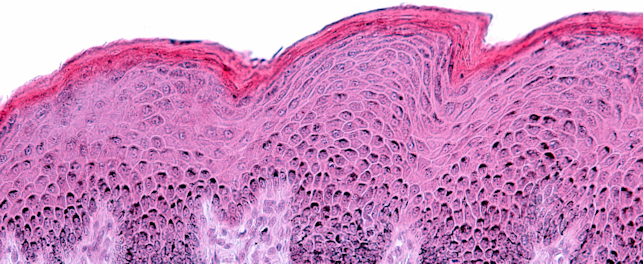

HDRS is a non-invasive test that combines both in vivo and in vitro processes to obtain a comprehensive understanding of efficacy. Through a non-erythemal (non-redness-inducing) optical assessment, it eliminates the need to induce erythema and pigmentation in subjects. In vitro measurements are fused with in vivo assessments to deliver instantaneous UVA-PF measurements, including a photostability assessment. In addition to being safer, HDRS offers faster turnaround times and is more cost effective.

Conventional in vivo sunscreen testing methods rely on exposing the skin to UV radiation to intentionally induce redness or pigmentation. While widely used and standardized, these methods raise ethical concerns. Meanwhile, fully validated in vitro alternatives that avoid human testing do not capture the essential factor of direct human skin exposure.